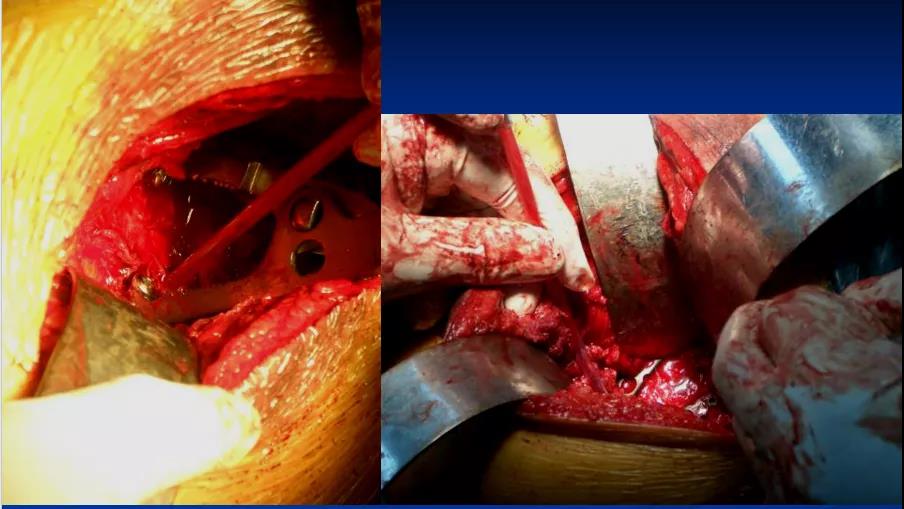

——典型案例——

微创插板病历后路有限切开,结合前路微创插板内